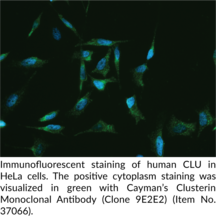

Clusterin is a secreted heterodimeric glycoprotein.{19214} It is proteolytically processed to remove a signal peptide and cleave the ? and ? chains.{19214,58474} This cleavage creates small- and medium-sized isoforms found in the nucleus or cytosol and mitochondria, respectively, and a large-sized isoform composed of ?- and ? chains linked via disulfide bonds near the center that is secreted outside the cell.{58474} Clusterin is ubiquitously expressed in tissues and found in physiological fluids. It is a multifunctional protein involved in a wide range of processes, including immune modulation, autophagosome formation, apoptosis, and extracellular matrix remodeling, among others.{58475} Clusterin is upregulated by cellular stress and acts as an extracellular chaperone and scavenger to prevent protein aggregation. SNPs in CLU, the gene encoding clusterin, are associated with a higher rate of cognitive decline in patients with mild cognitive decline or Alzheimer’s disease.{58476} Clusterin is also associated with inflammatory and cardiovascular diseases, where it has either protective or detrimental effects.{58474} Cayman’s Clusterin Monoclonal Antibody can be used for flow cytometry (FC), ELISA, immunocytochemistry (ICC), immunofluorescence (IF), and Western blot (WB) applications.

| Clone | 9E2E2 |

| Application(s) | ELISA, FC, ICC, IF, WB |